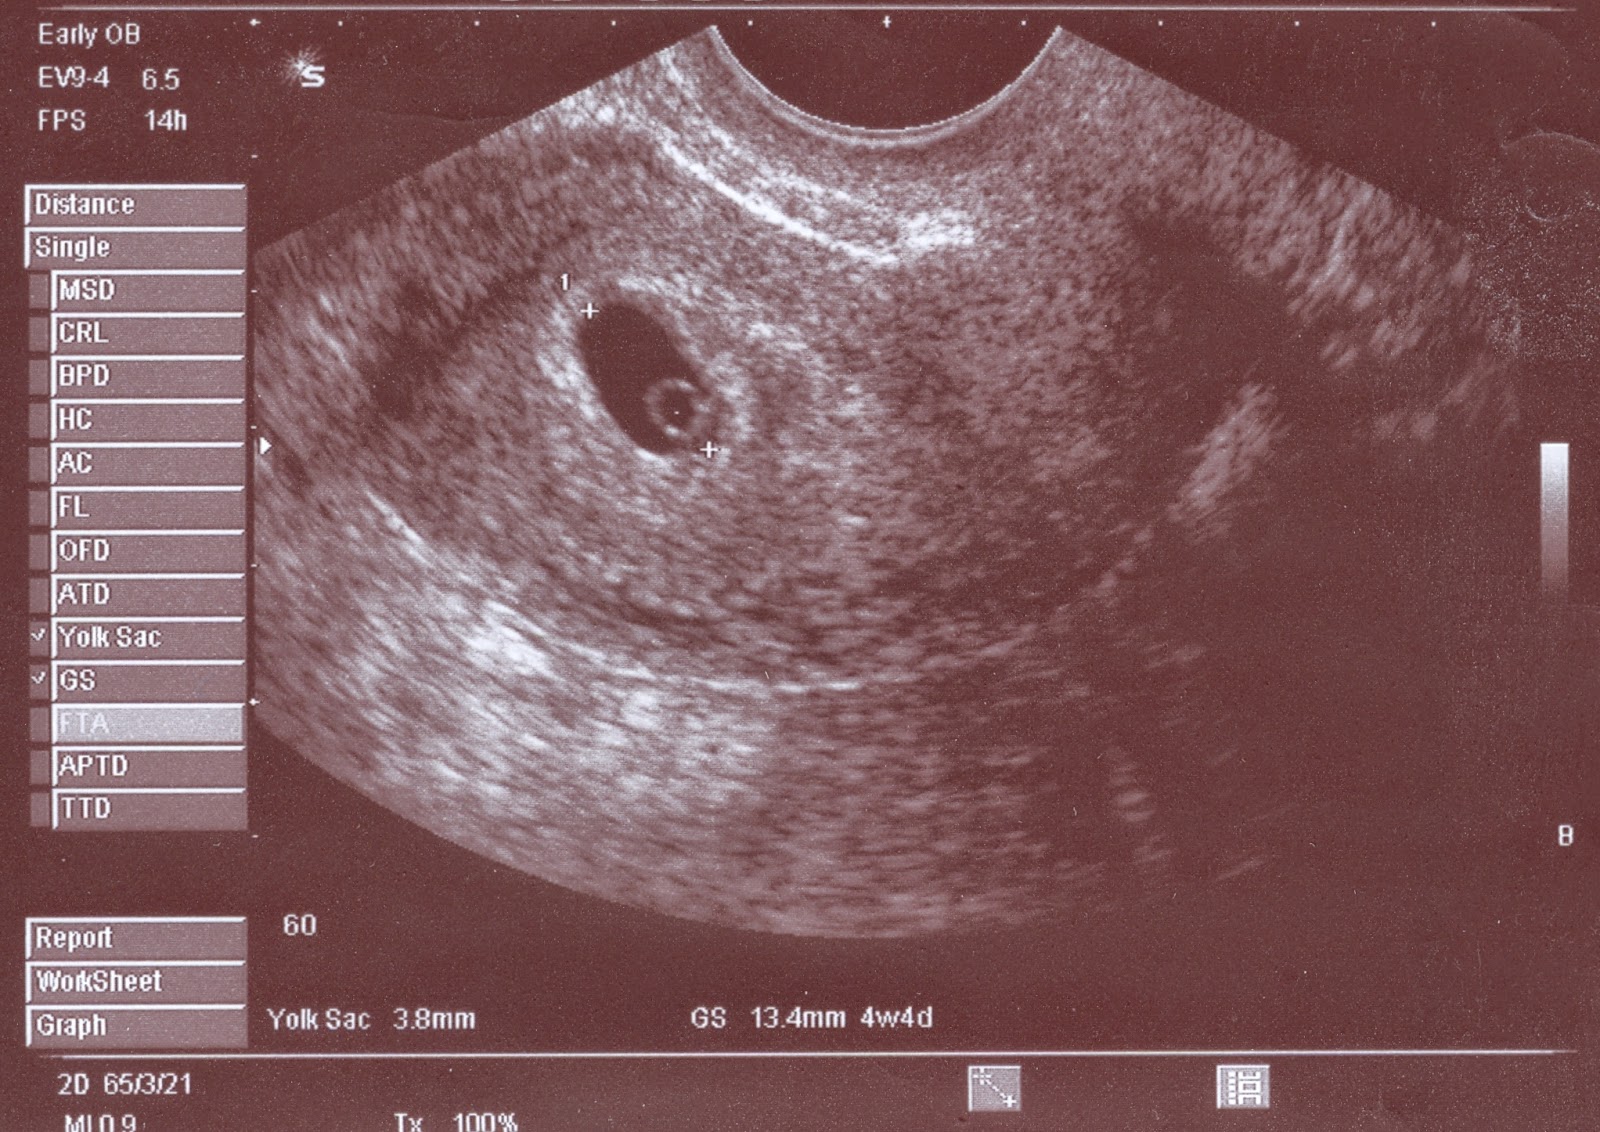

![]() |

| cztery tygodnie |